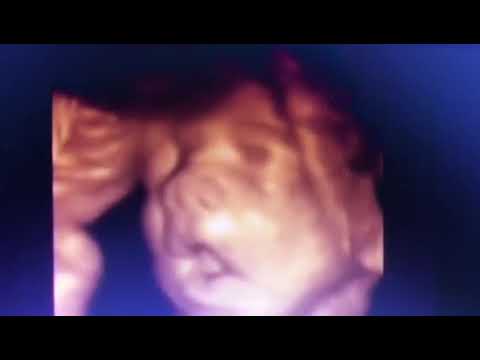

ECOGRAFIA 4D OBSTETRICA

ECOGRAFIA 4D OBSTETRICA ¿Cuándo se puede realizar una ecografía 4D y en qué casos está recomendada? Es recomendable que la ecografía se haga entre las semanas 26 y 32 de embarazo. Las ecografías son una rutina en todos los embarazos, hoy en día. La exploración con...